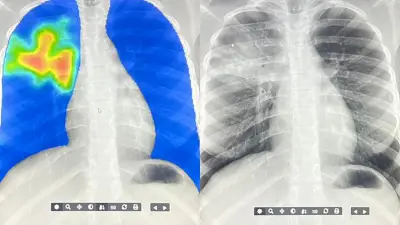

There's a global shortage of radiologists Now artificial intelligence is helping speed up the assessment of tuberculosis in hard-to-reach communities Image credit ARCAD Sant PLUS